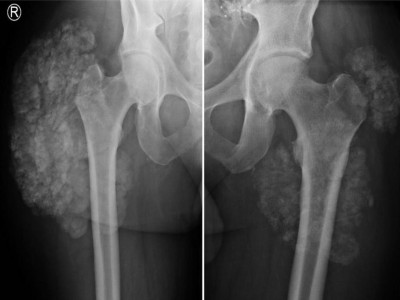

Warum nimmt die Oberschenkelschwellung beim Dialysepatienten immer mehr zu?

Bei einem 54-jährigen Mann nimmt seit einem halben Jahr die schmerzhafte Schwellung der rechten Hüfte bei bekannter Peritonealdialyse zu. Es besteht eine chronische Niereninsuffizienz. Vier Jahre zuvor war eine Parathyroidektomie bei tertiärem Hyperparathyreoidismus durchgeführt worden. Was zeigen Röntgen- und MRT-Bilder?

Chondroblastom in der MRT/© Camp L et al. / all rights reserved Springer Medizin Verlag GmbH, Patellafraktur/© K. Fehske · R. Hoffmann / all rights reserved Springer Medizin Verlag GmbH, Röntgenaufnahme eines nicht ossifizierenden Fibroms /© Weber M et al. / all rights reserved Springer Medizin Verlag GmbH, Cholesterolgranulom im MRT/© Frederik F/ all rights reserved Springer Medizin Verlag GmbH, pathologische distale Femurfraktur/© Omar M et al. / all rights reserved Springer Medizin Verlag GmbH, Frau unkenntlich fasst sich ans Knie/© Pornpak Khunatorn / Getty Images / iStock (Symbolbild mit Fotomodell), Echondrom/© Springer Medizin, Ausprägungen einer antiresorptivaassoziierten Kiefernekrose (AR-ONJ)/© Ristow, O. et al. / all rights reserved Springer Medizin Verlag GmbH, Stereotaktische Strahlentherapie (SBRT) einer solitären ossären Metastase in dem Brustwirbelkörper/© Springer Medizin Verlag GmbH, Arzt oder Pfleger schaut auf eine im MRT Eingang liegende Person/© [M] oksanazahray / stock.adobe.com (Symbolbild mit Fotomodell), Wirbelsäulenmetastase/© stockdevil / stock.adobe.com, Bluttransfusion/© Tobilander / Fotolia, Ärztin und kleines Mädchen mit Kopftuch/© FatCamera / Getty Images / iStock (Symbolbild mit Fotomodellen), Inhalt eines Fläschchens wird aufgezogen/© MarianVejcik / Getty Images / iStock, aneurysmatische Knochenzyste im Bereich des rechten distalen Femurs/© Springer Nature / all rights reserved Springer Medizin Verlag GmbH, Ewing-Sarkom/© Botos B. Z. et al. / all rights reserved Springer Medizin Verlag GmbH, Tumorkalzinose in der Hüfte/© Sukun A & Weber M.-A. , Computertomografie-gesteuerte periradikuläre Therapie auf Höhe von Lendenwirbelkörper 5/Sakralwirbelkörper 1 rechts/© Institut für Diagnostische und Interventionelle Radiologie des Klinikums St. Marien Amberg, Körperstereotaxie einer Lebermetastase im Segment VIII am MR-LINAC/© Ehret, F. et al. / all rights reserved Springer Medizin Verlag GmbH, Search Icon, Arthropedia, Ärzteteam führt Hüftoperation durch/© ATRPhoto / stock.adobe.com (Symbolbild mit Fotomodell), Gebrochener Fuß im Gips/© Aleksandr Kirillov / stock.adobe.com (Symbolbild mit Fotomodell)